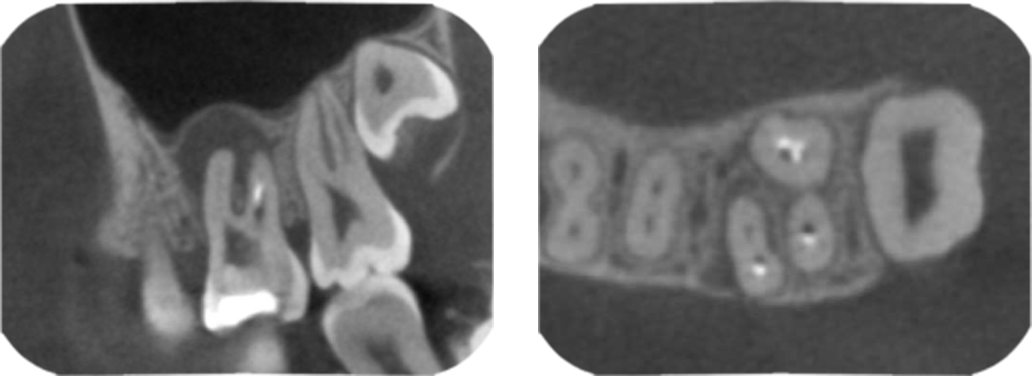

03 根管の構造を立体的に捉える 歯科用コーンビームCTで根管の隅々まで把握する

根管の構造を立体的に捉える歯科用コーンビームCTで根管の隅々まで把握する

根管の構造は一人ひとり少しずつ異なり、複雑です。歯科用コーンビームCTを使用し、根管の内部を3次元的にはっきり把握していきます。根管の形状や数など隅々まで構造を把握することで、勘や経験に頼らず、歯髄の除去が必要な部分が明確に分かり、的確に処置を進めることができます。

(歯科用コーンビームCTは治療上必要と判断された症例のみ撮影を行います。)